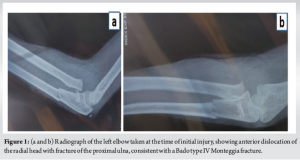

A young girl had a history of trauma to the left elbow during a school activity. The parents give a history of a fall on an outstretched hand planted firmly on the ground, suggestive of varus stress on the left elbow. There were no external wounds or distal neurovascular deficit in the upper limb. She had complaints of sudden onset pain, swelling, and restriction of movements in the left elbow. She was taken to a local hospital wherein radiographs were taken (Fig. 1) and was managed conservatively with above elbow plaster of paris application for 4 weeks (Fig. 2). She presented to our out patient department almost 1 year post the injury with complaints of pain on rest and pain at terminal flexion and extension with restriction of movements of her left elbow.